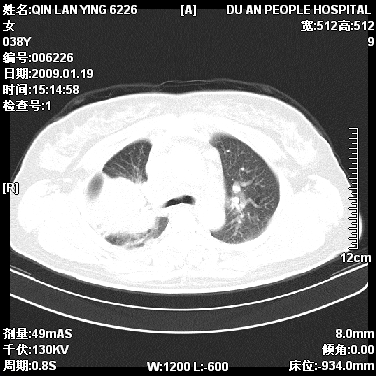

女,38岁,胸疼1个月。wbc:1万4

1)右肺中央型肺癌并右肺上叶阻塞性肺炎、节段性肺不张,纵隔淋巴结转移、右侧胸膜转移、肝脏转移。2)右侧胸腔少量积液。

1、右侧中央型肺癌并阻塞性肺不张,纵隔内、主动脉弓旁、右肺门淋巴结及肝脏转移可能性大,建议纤支镜进一步检查。

2、右侧胸腔积液。

本病例有几个容易诊断的地方:1、右肺上叶前段支气管闭塞,肺不张。2、淋巴结明显肿大。3、肝脏多个类圆形低密度影呈“牛眼征”改变,高度提示转移。

从影像学角度分析      右肺上叶中央型肺癌,并阻塞性不张、肺炎,纵隔淋巴结、膈顶淋巴结转移。

肝内两个大小不等低密度结节,内可见更低密度影,首先考虑肝内转移瘤,但联想到患者wbc1万4,建议楼主还是做个增强比较明确,除外肝脓肿的可能。